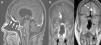

Case reportOur patient was a 65-year old female with anosmia and cognitive deterioration. Cranial MRI showed a large tumoral lesion with solid and cystic components involving the nasal cavity, with diagnostic suspicion of intracranial malignant sinonasal tumour. The patient underwent a fully endoscopic transcribiform-transfovea ethmoidalis EEA, achieving total resection and tumour-free margins. Surgery was followed by radiotherapy.